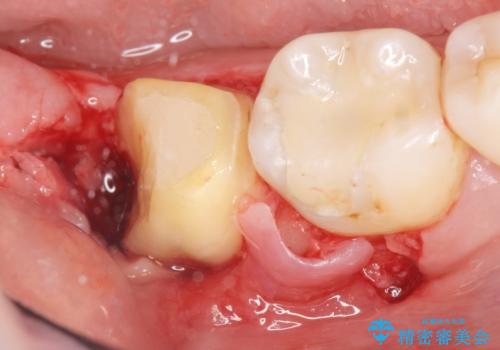

精査したところ、右下の一番奥の歯(右下7)に歯肉縁下に及ぶ深いう蝕を認めました。

神経がない歯であり痛みが出ないことから、自覚症状がほとんどなくう蝕が大きく進行してしまったと考えられます。

銀歯を除去し、歯周外科処置(右下7遠心の骨整形及びディスタルウェッジ)を行った後にメタルボンドクラウンによる補綴を行いました。